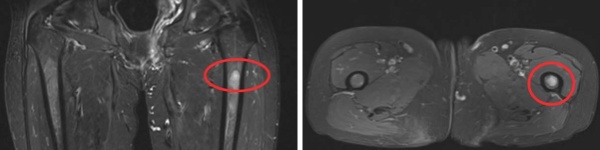

MRI 影像:左股骨髓腔内可见明确异常信号,病灶范围清晰可见;

CT 扫描:骨质破坏特征显著;